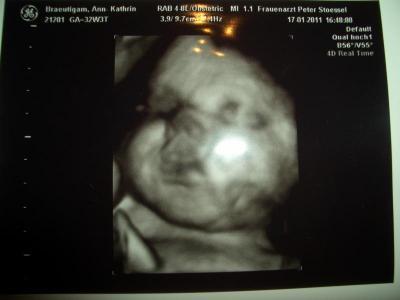

War heut beim FA und wollte euch mal meine BauchMaus zeigen

Es ist alles okay! ABER sie ist von der Entwicklung her 2 Wochen vorraus. Wäre demnach schon in der 35ssw. Sollte mich drauf einstellen das sie evtl. schon im Februar kommt. Nächste Woche muss ich wieder zum CTG- bisher habe ich noch keine Wehen.

Bild zu War heut beim FA und wollte euch mal meine BauchMaus zeigen - Forum für März - Mamis

Wie groß weiß ich leider nicht, hat der Doc heut nicht gesagt. Nur Gewicht und das liegt bei gut 2500g! Wenn ich überleg das mein Sohn bei der Geburt 2660g hatte (geboren bei 36+0) ohweia, dann wird diese ne Wuchtbrumme

Unser Sohn kam auch bei 36+? mit 2665g Hihi, 5 gramm mehr.... Dein Ultraschallbild ist wirklich total